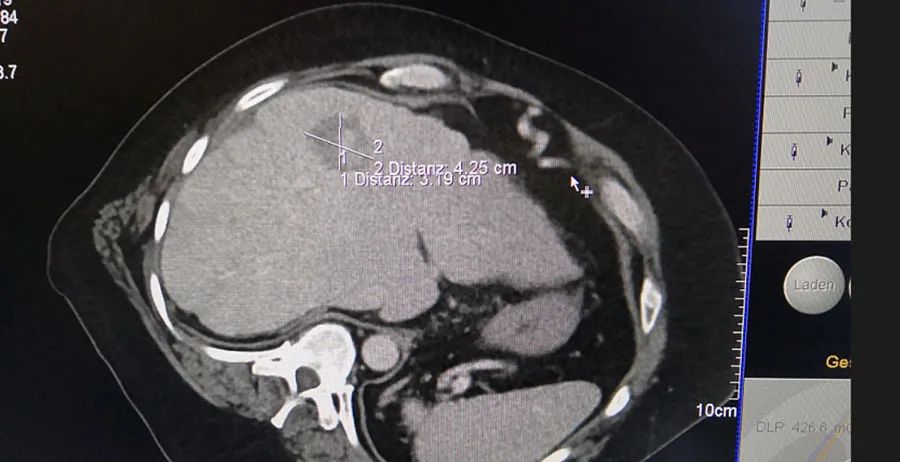

两例微波消融手术均在肝脏进行,病灶紧贴血管和胆管,手术环境非常复杂,手术难度系数极高。但是,得益于我们微波消融天线的专利反相位技术、精准控制技术以及全天线水冷技术,消融区域得到了很好的控制,由此有效实现了肝脏肿瘤的精准消融。结合影像资料我们可以看出,消融区域的圆率非常高,并且消融后毗邻病灶的血管与胆管几乎没有受到损伤。

术中影像资料